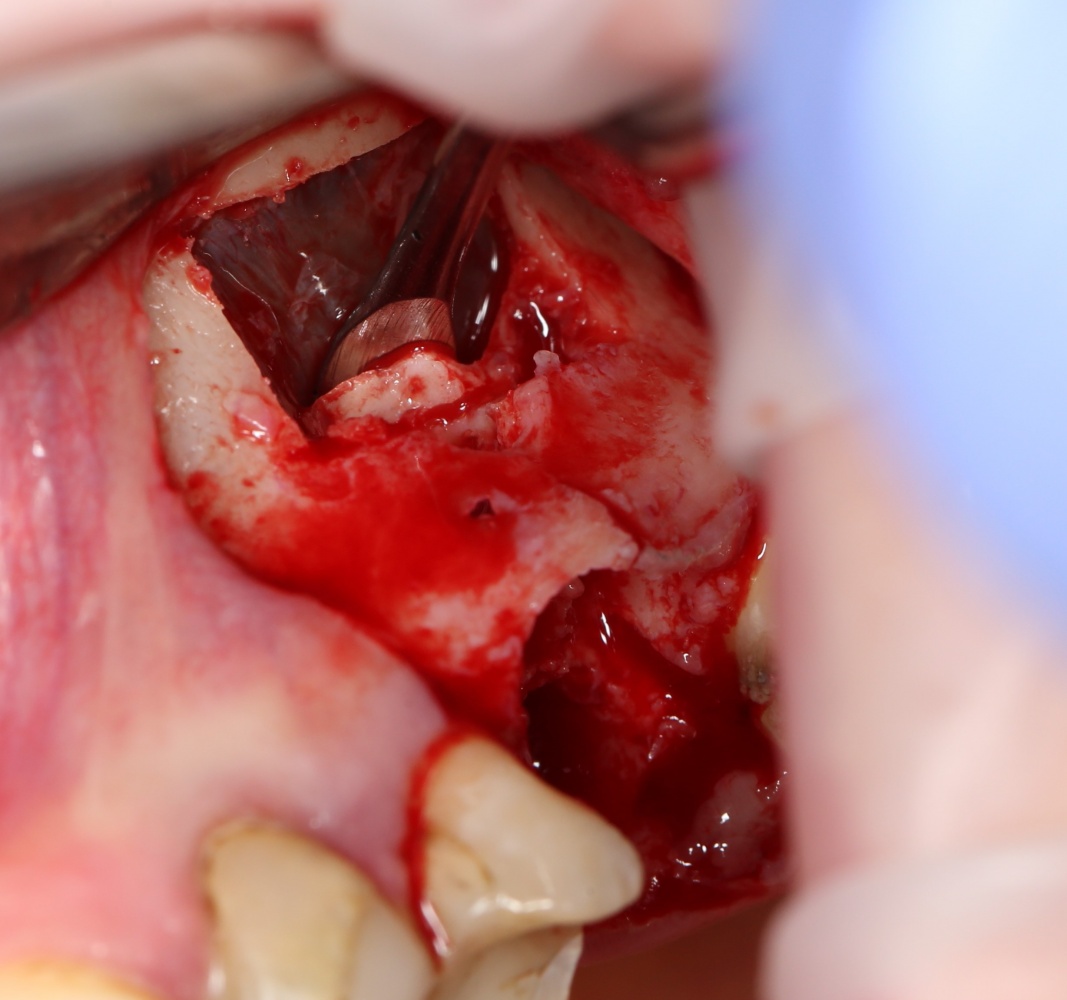

Синуслифтинг: что делать при перфорации слизистой оболочки гайморовой пазухи?